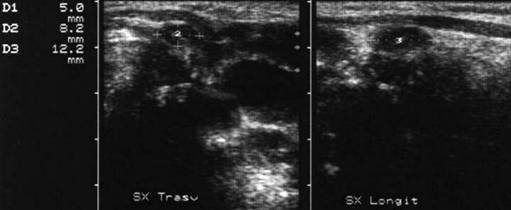

Lob stg. in proiectie longitudinala si trasversala.

Femeiede 49 ani.

Mic nodul calcificat in lobul stang al tiroidei.

Este vizibil o imagine circulara hiperecogena, cu con de umbra posterioara.

Lob stang in proiectie longitudinala si trasversala.

Femeie de 61 ani. Mic nodul

calcificat localizat paraistmic anterior in lobul stang, de 7x8mm.

Este evident conul

de umbra posterioara.